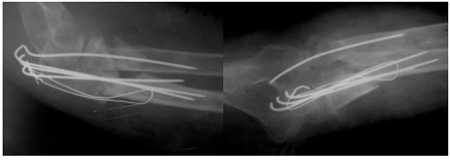

Во всех перечисленных случаях применялась дополнительная гипсовая иммобилизация от двух до четырех недель. В 22(24,4%) случаях применял-ся остеосинтез длинным губчатым компрессирую-щим винтом, из которых в 14(15,5%) случаях имел место поперечный перелом, в 5-и(5,5%) - оскольчатый (рис.2), в 3-х(3,3%) - раздробленный, двое из которых нуждались в дополнительной фиксации специально разработанной нами пластинкой и вторым винтом (рис.3).